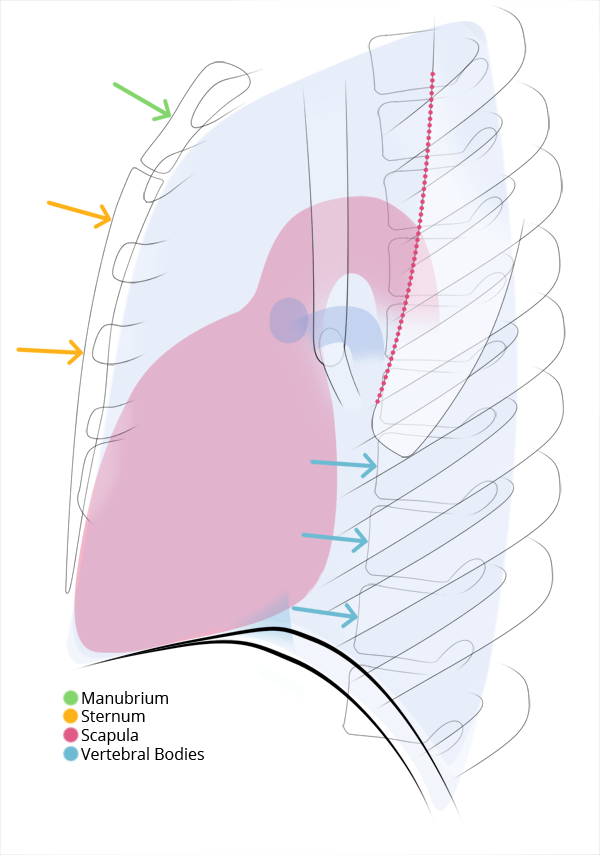

Chest

Chest

Chest radiograph & CT anatomy

Chest

Chest

Chest radiograph & CT anatomy